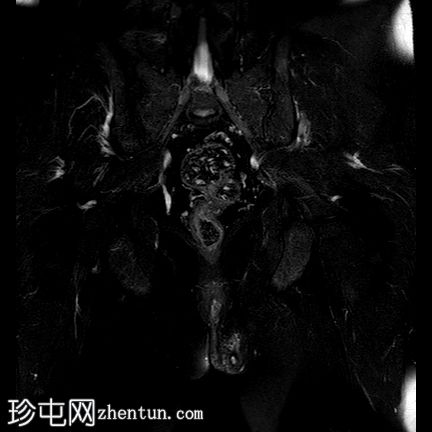

冠状位T1加权像

增强脂肪抑制像

一条低T1信号、高T2/PD信号的弧形瘘管连接肛门黏膜和左侧会阴皮肤,并伴有明显的管状强化。该瘘管从肛门黏膜后方6点钟方向穿过肛门内括约肌,然后穿过括约肌间隙,但未穿过肛门外括约肌。皮下少量积液提示脓肿形成。上述影像学表现符合2级括约肌间肛周瘘。

根据圣詹姆斯大学医院的分类,这是一例活动性 2 级括约肌间肛周瘘 1 型病例。